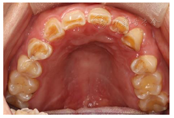

(1)面部检查:面部外形不对称,颏部居中,两侧口角高度不一致,面下1/3高度减小,两侧颧弓突度一致,下颌前突。中位笑线,上唇长度适中(图1)。(2)关节检查:颞颌关节:弹响(-),杂音(-),疼痛(-)。开口度正常,开口型有偏斜,肌肉触诊压痛:右侧上颌结节(+)、左侧上颌结节(++)、双侧翼内肌(+),其他肌肉及颞下颌关节区未诉异常,关节载荷实验无任何紧张和疼痛不适。(3)口内检查:上下颌牙中线较面中线向右偏斜,前后牙广泛不均匀磨耗,前牙磨耗后呈刃状;14、21、22、23及下颌牙唇颊侧颈部见釉质缺损,部分牙本质暴露,呈黄褐色,少量白垩色;44牙见开髓孔,表面暂封。12缺失,缺失牙间隙无。全口牙龈色形质未见异常,11牙、21牙唇侧牙龈龈缘高度不一致,21牙较11牙龈缘高约3mm。全口口腔卫生状况良好,菌斑、软垢少量,未及牙石及牙周袋。咬合检查:11-14牙与对颌牙反

,21牙与31、31牙对刃,左侧尖牙至前磨牙深覆盖,

曲线不平(图2,图3)。(4)影像学检查: